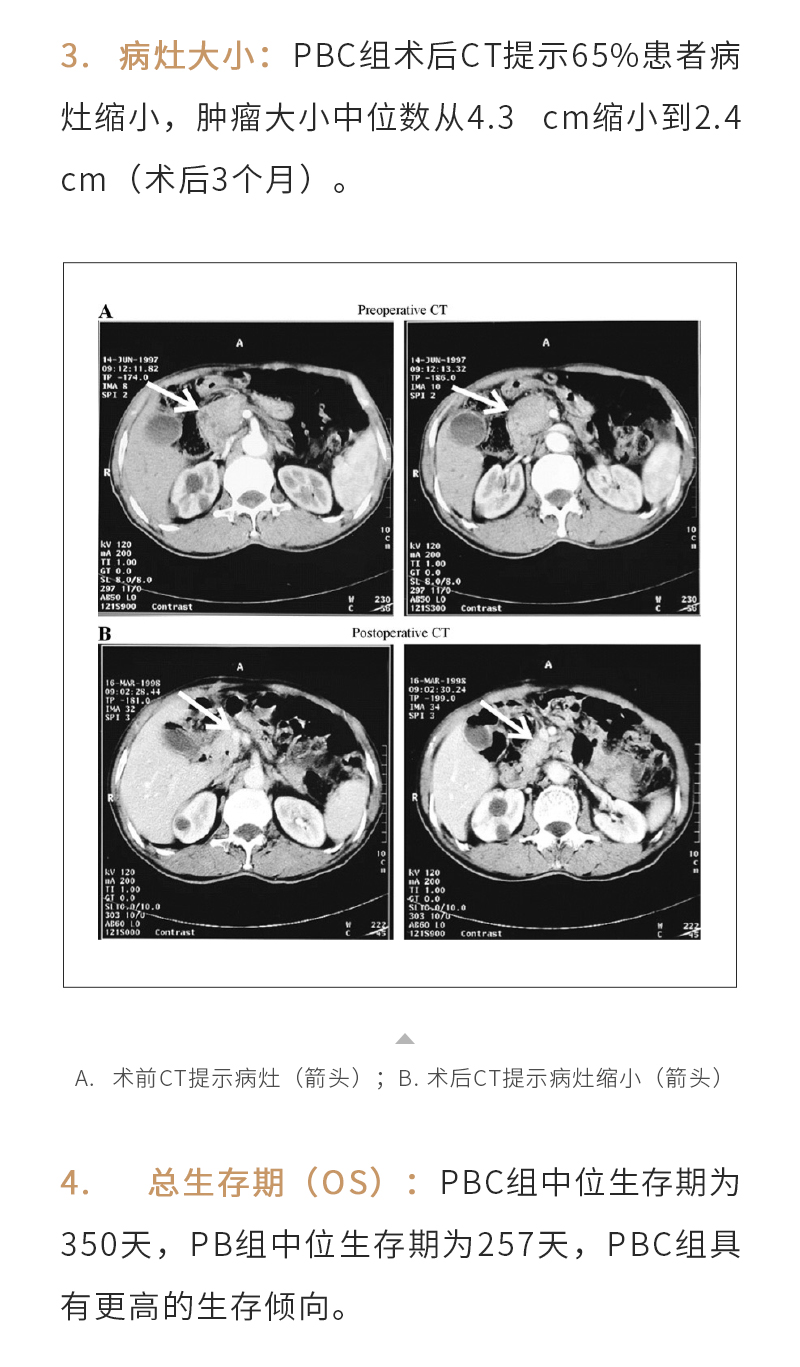

產品介紹

新聞動態